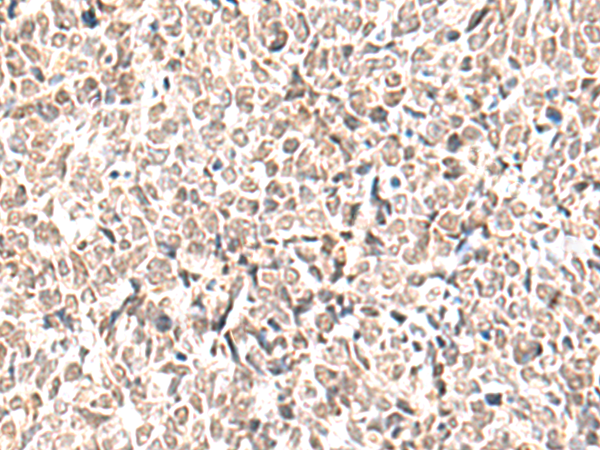

分类: 科研抗体货号: P10118别名: QA1; HLA-6.2应用: IHC反应种属: Human